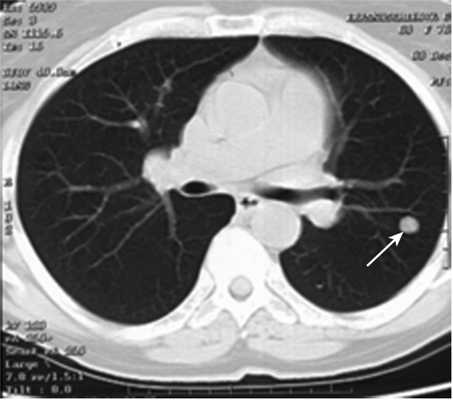

Все больные были разделены на группы в зависимости от размера очагового образования: 1-ю группу (диаметр ООЛ 0,5-1; рис. 1) составили 9 мужчин и 14 женщин, 2-ю группу (диаметр ООЛ 1-2 см; рис. 2) - 30 мужчин и 13 женщин, 3-ю группу (множественные ООЛ; рис. 3) - 27 мужчин и 17 женщин.

Рис. 2. Компьютерная томограмма груди пациента 2-й группы.